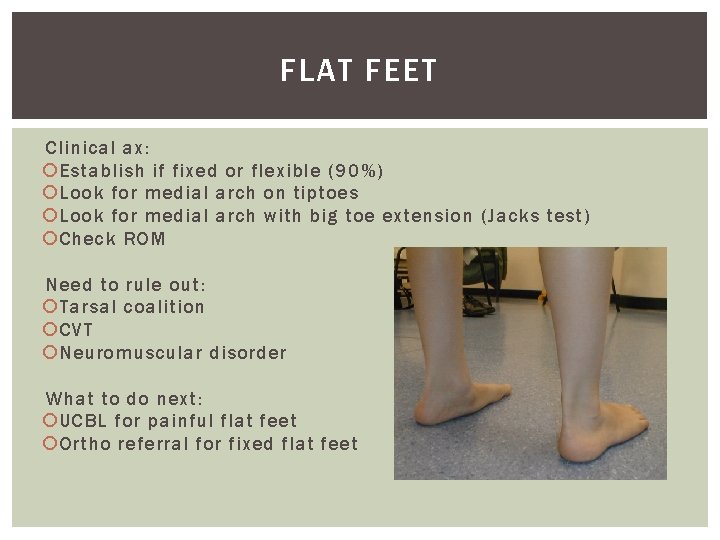

FLAT FEET Clinical ax: Establish if fixed or flexible (90%) Look for medial arch on tiptoes Look for medial arch with big toe extension (Jacks test) Check ROM Need to rule out: Tarsal coalition CVT Neuromuscular disorder What to do next: UCBL for painful flat feet Ortho referral for fixed flat feet